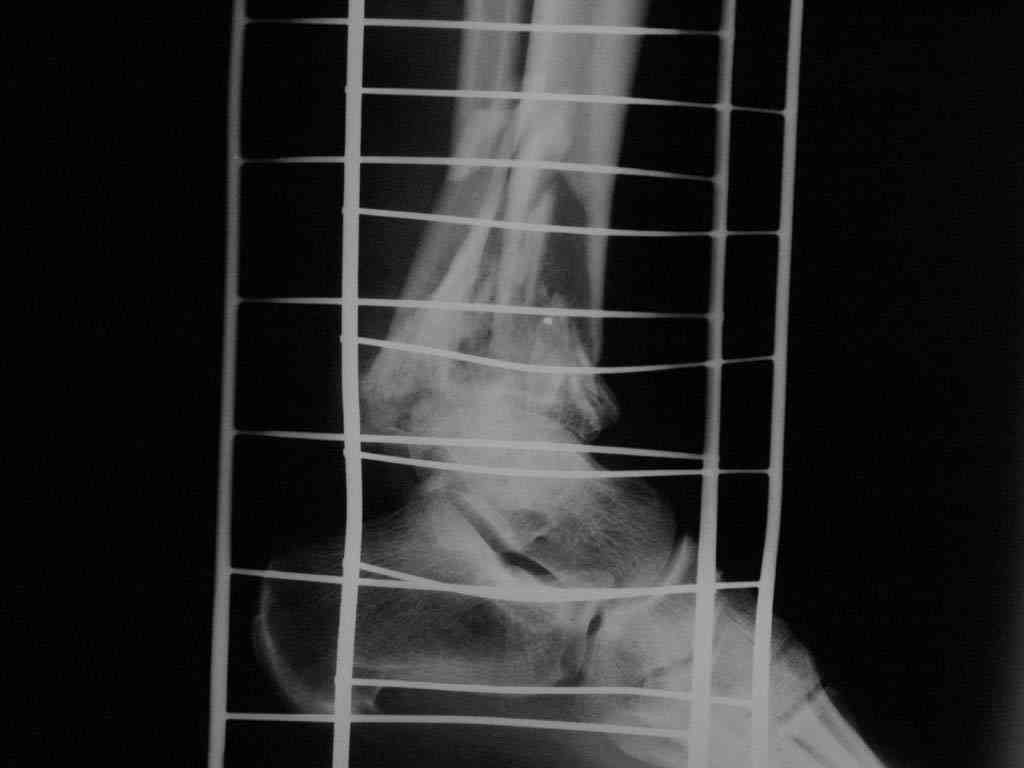

Больной А, 40 лет, находится в клинике с 15.10.08 с диагнозом: <br />Сочетанная травма. Ушиб головного мозга лёгкой степени тяжести. Компрессионные переломы тел 12 грудного и 5 поясничного позвонков без неврологических осложнений. Закрытый внутрисуставной многооскольчатый перелом дистальных метаэпифизов обеих костей правой голени со смещением. Открытый внутрисуставной многооскольчатый перелом дистальных метаэпифизов обеих костей левой голени со смещением (см. Р-граммы). Хронический алкоголизм.

При поступлении состояние тяжелое. Глубокое оглушение. Дыхание самостоятельное, адекватное. Гемодинамика стабильная. По внутренней поверхности левой голени, в нижней трети, рвано-ушибленная рана 10-6 см, из раны выстоит проксимальный отломок большеберцовой кости, рана обильно загрязнена землёй. Интенсивная терапия в условиях реанимационного отделения, вытяжение за правую пяточную кость, параартериальная блокада обеих нижних конечностей, гипсовая лонгета на левую нижнюю конечность, ас-повязка на рану.

Через 4 часа после поступления оперирован: после неоднократного промывания раны тёплой проточной водой с мылом, антисептиками, при ревизии определяется земля в канале проксимального отломка на глубину 3 см..., отсутствие надкостницы на концах дистального и проксимального отломков на 3 см. Удалено значительное количество мелких костных фрагментов, перемешанных с землёй, выполнена ПХО раны, резекция проксимального конца большеберцовой кости на 3,5 см, ЧКДО аппаратом Илизарова. Рана не ушивалась.

Представляем рентгенограммы левой голени при поступлении, после повторного оперативного лечения и фото st.localis на 14.11.08.